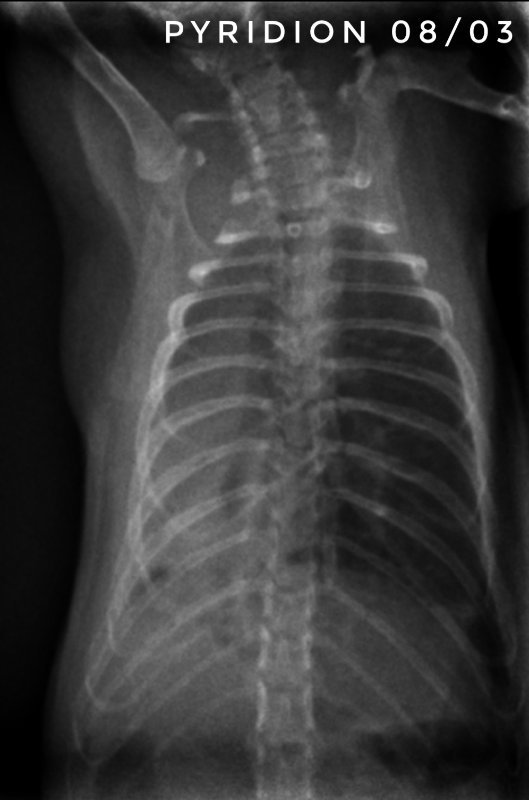

Toujours pour ceux que ça intéresse, les dernières  radios et le suivi du poids (Pyridion a commencé à perdre du poids le 04 mars, traitement changé le 08)

Pyridion a eu un vrai mieux la semaine dernière et grosse dégradation là. Les radios n'ont pas bougé depuis 3 semaines...

Bon, Drupe et Caryopse continue de prendre du poids régulièrement, mais Pyridion est en chute libre... Entre le 1er et le 4 mars, il a pris de 220 à 230g, on était super contents, puis il a perdu petit à petit, le 8 il n'était plus qu'à 215g, on a changé de traitement, il est aujourd'hui à 197g... Mardi et jeudi il avait repris un peu donc comme j'ai eu du mal à bien lui donner le marbofloxacine (seule la citation des molécules actives est autorisée) au début, je me suis dit que ça commençait à faire effet, mais en fait il continue à perdre... je contacte mon veto demain (la prochaine visite était prévue le 28...).